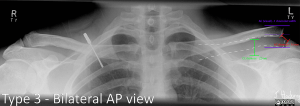

Grade III

The inferior border of the clavicle is raised in respect to the acromion above its superior border.

Comparative views can be useful if you are clinically suspicious of an ACJ injury, but normal AP views are not conclusive.